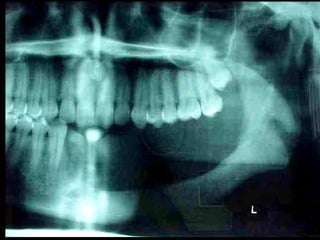

Trismus importante debido a que

El tumor ya rompió el hueso com-

Pacto de la cara interna de la

Mandíbula y empezó a tomar el

Músculo pterigoideo interno y

milohioideo.

Límite tumoralLímite tumoral

Area de lisis ósea a nivel de la línea

Miliodes que contracturó los músculos

Milohioideo y pterigoideo interno

Dificultando la deglución y determinando

Trismus importante.